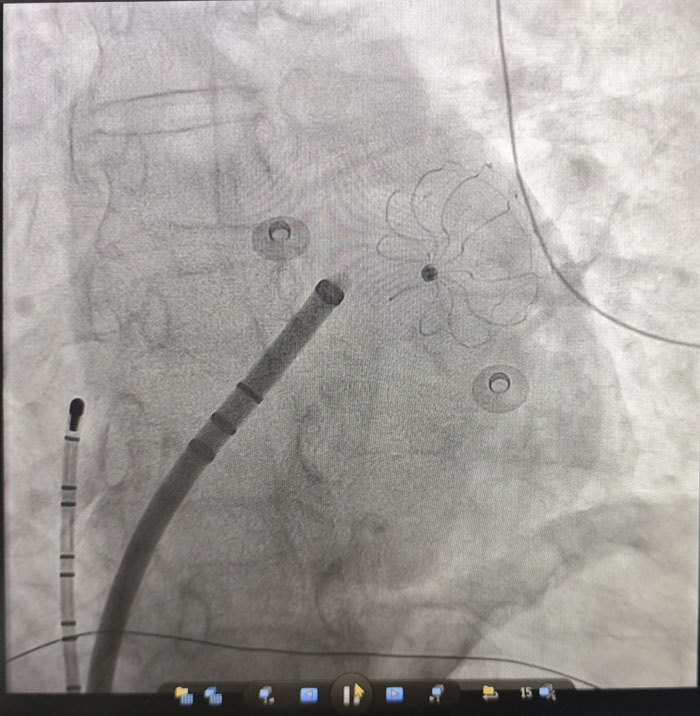

在房顫治療方面,團隊成功開展“房顫射頻消融+左心耳封堵”一站式手術。患者為67歲女性,受房顫困擾多年,心悸、胸悶反復發作,生活質量嚴重下降,同時面臨高卒中風險。傳統房顫治療通常需分別處理心律轉復與抗凝問題,過程繁瑣,對患者依從性要求較高。經全面評估與多學科討論,團隊決定采用微創介入技術,在一次操作中同步解決兩大問題:射頻消融精準定位并消除心臟內引發房顫的異常電信號,幫助恢復竇性心律,從根源上改善心慌、胸悶等癥狀;同時針對房顫患者約90%的血栓來源于左心耳的特點,植入封堵器封閉這一“血栓工廠”,從源頭上預防腦卒中等血栓栓塞事件。

手術過程順利,術后復查顯示,患者心律已恢復為正常的竇性心律,左心耳封堵器位置良好、無殘余分流。次日,患者即可下床活動,恢復迅速。該一站式診療方案,為高卒中風險、高出血風險,或無法耐受長期服藥的房顫患者,提供了一次手術、雙重獲益的優質解決方案。